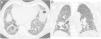

“Alternative diagnosis”: In some cases of fibrotic lung disease, there is clinical suspicion of IPF, but the HRCT pattern suggests an alternative diagnosis (Fig. 4). Examples include bronchocentric fibrosis in the upper lobes or profuse mosaic attenuation that suggest hypersensitivity pneumonitis, posterior fibrotic retraction of the hila in sarcoidosis, or extensive ground-glass opacification with subpleural sparing in fibrotic nonspecific interstitial pneumonia (NSIP).

Figure 4.CT images in a case with an alternative diagnosis — in this case fibrosing NSIP. (A + B) show axial slices with interstitial parenchymal changes, but no honeycombing and marked ground glass opacification. Coronal reformats (C) show the distribution of the disease being more uniformly distributed between upper and lower lung areas. (D) shows a coronal CT image in expiration with sharply demarcated areas of air trapping.